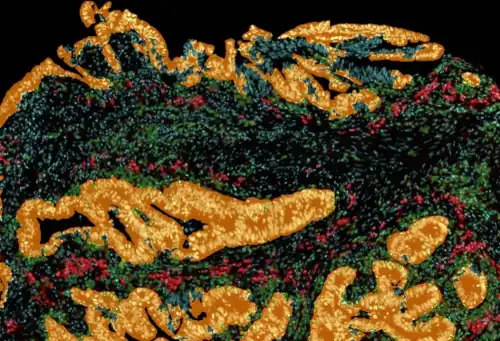

Tissue image cytometry or tissue cytometry is a method of digital histopathology and combines classical digital pathology (glass slides scanning and virtual slide generation) and computational pathology (digital analysis) into one integrated approach with solutions for all kinds of diseases, tissue and cell types as well as molecular markers and corresponding staining methods to visualize these markers. Tissue cytometry uses virtual slides as they can be generated by multiple, commercially available slide scanners, as well as dedicated image analysis software – preferentially including machine and deep learning algorithms.[1] Tissue cytometry enables cellular analysis within thick tissues, retaining morphological and contextual information, including spatial information on defined cellular subpopulations.[2]

In this process, a tissue sample, either formalin-fixed paraffin-embedded (FFPE) or frozen tissue section, also referred to as “cryocut”, is labelled with either immunohistochemistry[3](IHC) or immunofluorescent markers, scanned with high-throughput slide scanners and the data gathered from virtual slides is processed and analyzed using software that is able to identify individual cells in tissue context automatically and distinguish between nucleus and cytoplasm for each cell.[1] Additional algorithms can identify cellular membranes, subcellular structures (like cytoskeletal fibers, vacuoles, nucleoli) and/or multicellular tissue structures (glands, glomeruli, epidermis, or tumor foci).[4]Fluorescence Activated Cell Sorting (FACS) is a method of analysis that measures fluorescence signals on single cells, where the signal comes from antibody-mediated staining techniques and phenotypes detected by flow cytometry.[5] The major limitation of flow cytometry is that it can only be applied – as the name suggest – to cells in solution. Although methods of “solubilizing” solid tissue exist, any such processing irrevocably destroys the tissue architecture and any spatial context. Hence, tissue cytometry complements the use of flow cytometry and fluorescence microscope[6] in basic research, clinical practice, and clinical trials by providing FACS-like analyses on solid tissue sections (as well as adherent cell cultures) in situ. The advantage of tissue cytometry against flow cytometry is that tissue cytometry does not require the cells to be suspended in fluid, aiding in maintaining the integrity of the tissue structure, morphology, and contextual information, further assisting in precise and accurate contextual analysis that are not possible in flow cytometry.

A more robust and automated system was designed to perform flow cytometry-like analyses on immunostained cells in a fixed tissue and termed tissue cytometry.[7] The technique was introduced in the 1990s based on patents by Steiner and Ecker,[8] describing a procedure for “Cytometric Analysis of Diverse Cell Populations in Tissue Sections or Cell Culture Visualized Through Fluorescence Dyes and/or Chromogens". Tissue cytometry emerged as a transformative extension of digital pathology, promising to bridge the gap between image-based analysis and quantitative, data-driven insights. At its core, tissue cytometry enables the automated and quantitative analysis of cellular and tissue features. By employing computational algorithms and machine learning models, it can accurately segment nuclei, identify cell types, and quantify protein expression levels within the tissue context.

Tumor Microenvironment: Tissue cytometry is heavily used in research to characterize the tumor microenvironment including e.g. identification of the immune landscape or tumor-vascularization, within IHC/IF-processed tissue sections. One reason is that by using this technology the complex tissue architecture stays intact and therefore also spatial relationships between cellular phenotypes and/or multicellular structures can be analyzed.[14]